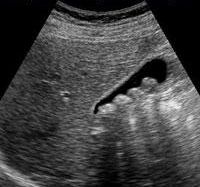

Το υπερηχογράφημα έχει μεγάλη διαγνωστική ακρίβεια στην περίπτωση της οξείας χολοκυστίτιδας και έχει υποκαταστήσει τη χολοκυστογραφία η οποία γινόταν παλαιότερα. Η υπερηχογραφική εικόνα της οξείας χολοκυστίτιδας είναι χαρακτηριστική. Η χοληδόχος κύστη είναι διατεταμένη, με παχύ τοίχωμα, περιέχει δε λίθους και ίζημα. Περιχολοκυστικό οίδημα υπάρχει επίσης σε πολλές περιπτώσεις.